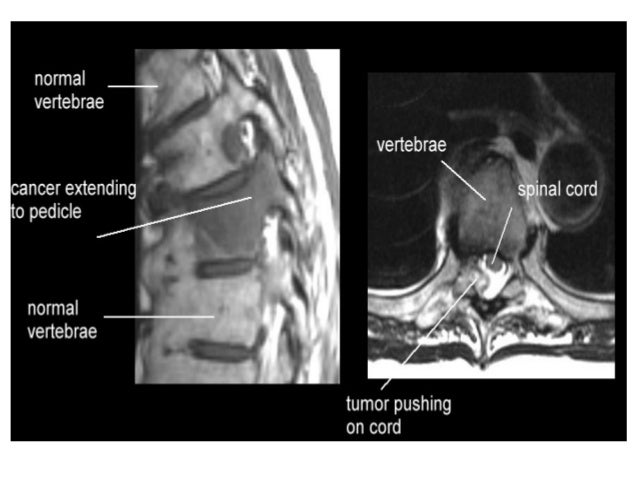

Compression of the spinal cord is due

predominantly to extradural metastases

(95%) and usually results from tumor

involvem...

MRI